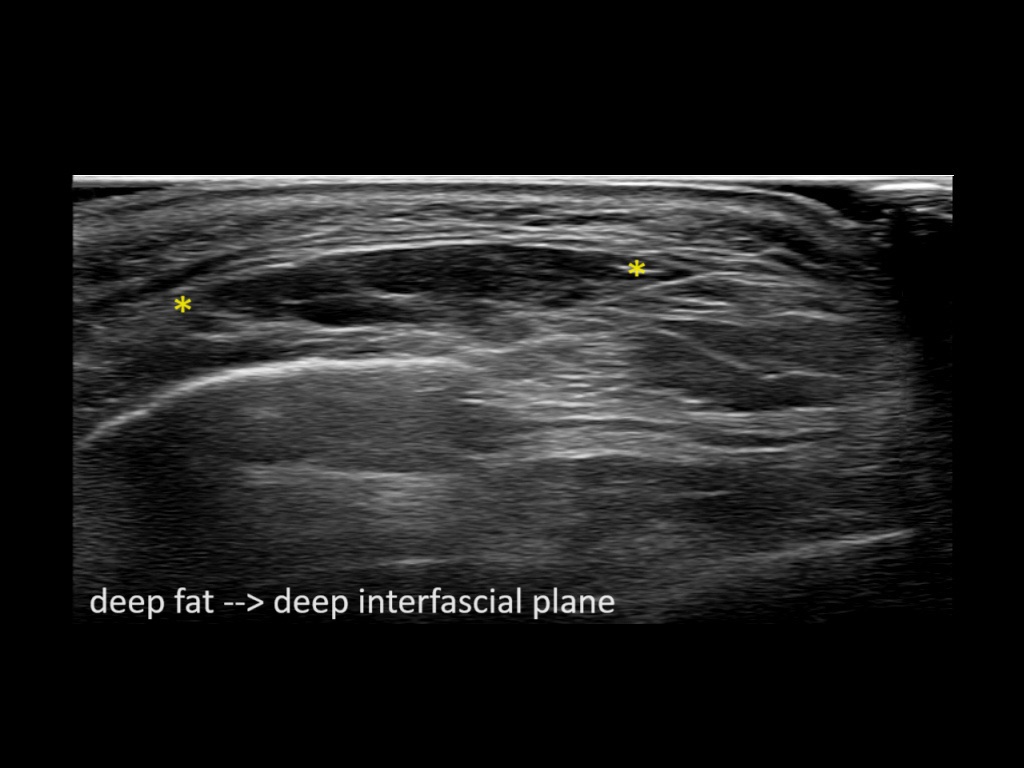

Filler behavior - Temple zygoma US

Study the first image to recognize the different layers. If you are sure about the layers, swipe to the second image to view the answer (if applicable).

Hover over an image to view the secondary image or click on the image title for more information.